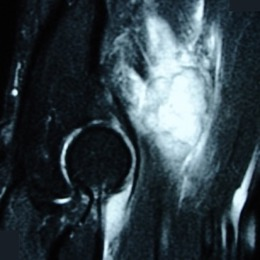

Radiographic imaging is used to help form a diagnosis. These include X-Ray, MRI, CT and Bone Scans.

An example of an MRI is shown.

MRI of a Clear Cell Sarcoma